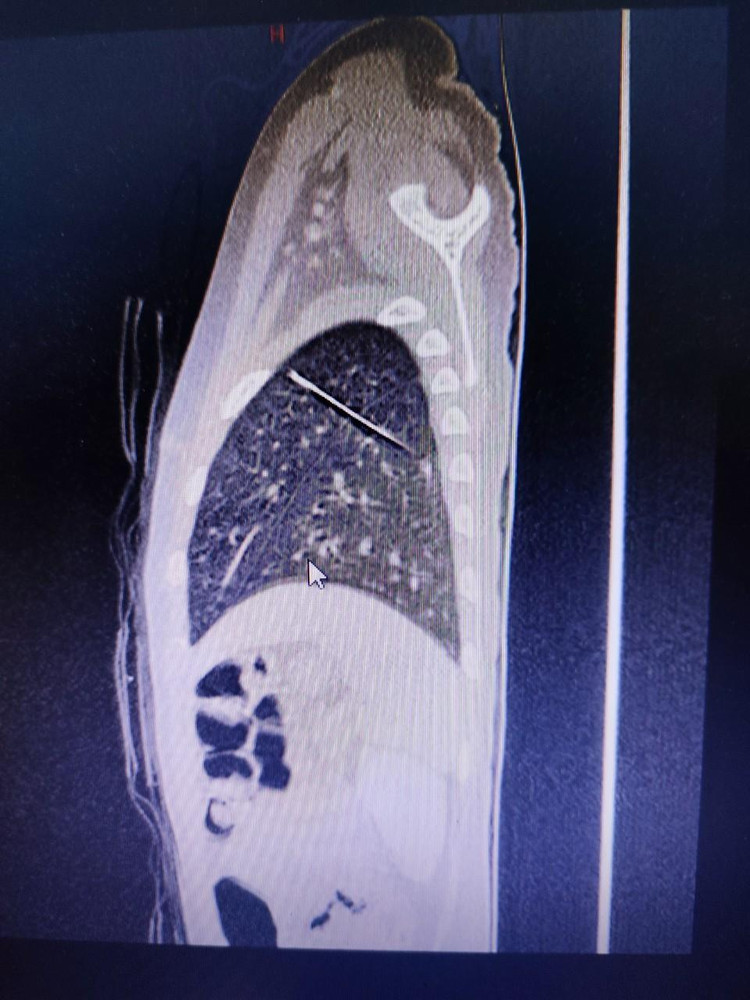

Tại đây, bé được thăm khám và tiếp tục được chụp CT scan, ghi nhận dị vật hình dạng kim may áo quần, nằm trong nhu mô phổi trái, xuyên từ thùy dưới lên thùy trên.

| Ảnh chụp cho thấy rõ vị trí chiếc kim may áo quần trong phổi của bé |